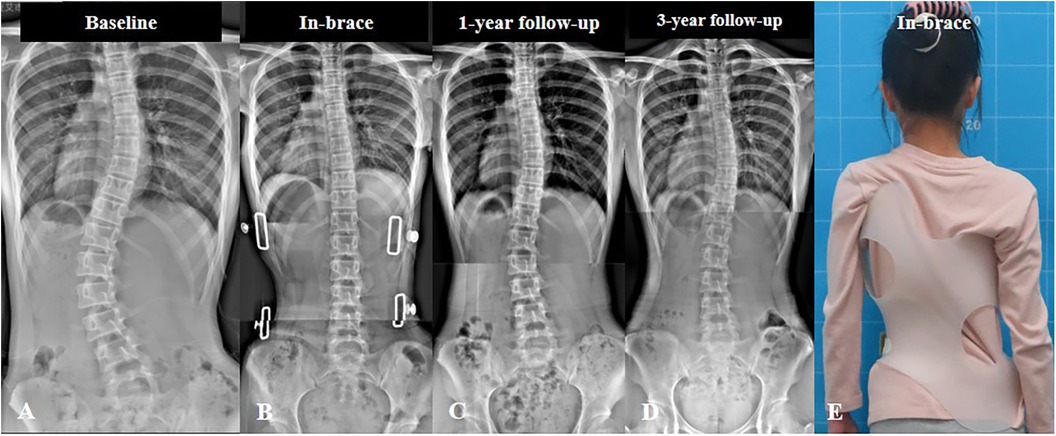

يُعد الحزام الطبي أحد أكثر الطرق فعالية لعلاج اعوجاج العمود الفقري عند المراهقين ومنع تفاقم الانحناء خلال مرحلة النمو. ومع اقتراب انتهاء فترة العلاج، يتساءل الكثير من الأهل: ماذا يحدث بعد إزالة الحزام؟ هل سيعود الانحناء؟ وكيف يمكن متابعة الحالة والحفاظ على النتائج؟ هذا المقال يقدّم إجابات مفصلة بطريقة سهلة الفهم للأهل، مع التركيز على الوقاية والمتابعة بعد التوقف عن الحزام.

تشير الدراسات إلى أنّ الانحناء قد يعود بعد إزالة الحزام، لكنه عادةً يمر بعدة مراحل:

بعد إزالة الحزام مباشرة، قد تُسجَّل زيادة متوسطة في زاوية كوبب بمعدل درجات بسيطه. هذا أمر طبيعي ويُعتبر جزءًا من استجابة الجسم للتوقف عن الدعم الخارجي.المرحلة قصيرة الأمد (حتى 5 سنوات):

خلال هذه الفترة، قد يزداد الانحناء بمعدل تقريبي 0.8 درجة سنويًا، لذلك يُنصح بالمتابعة الدقيقة مع الطبيب لملاحظة أي تغيّر في زاوية الانحناء أو شكل الظهر.المرحلة الطويلة الأمد (بعد 5 سنوات):

يقل معدل تفاقم الانحناء تدريجيًا ليصل إلى حوالي 0.2 درجة سنويًا، خاصة إذا كان المراهق ملتزمًا بالتمارين الموصوفة والمتابعة الطبية الدورية.

بعد إزالة الحزام الطبي، يعتمد معدل عودة الانحناء على حجم الاعوجاج عند التوقف والتزام المراهق بالتمارين والمتابعة الطبية. كلما كانت الزاوية أصغر عند إزالة الحزام، قلت فرصة تفاقم الانحناء. لذلك، يُنصح بالمتابعة المنتظمة مع الطبيب، لضمان عمود فقري صحي ومستقيم على المدى الطويل.